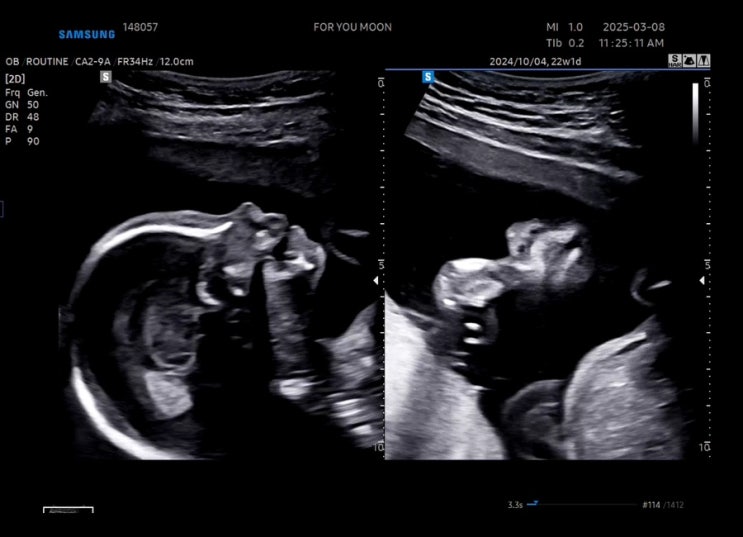

임신 20주-22주차 기록_요란해지는 태동, 배나옴, 정밀초음파

임신 20주차, 21주차, 22주차의 기록 내가 벌써 임신 중기라니! 시간이 잘도 가는만큼 다행히 가지도 잘 크...